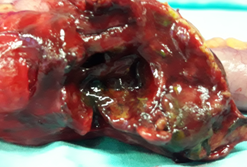

Μακροσκοπική άποψη μετά από χειρουργική εκτομή νεκρωτικού ιστού (Ευγενική παραχώρηση Dr. V. Penopoulos)